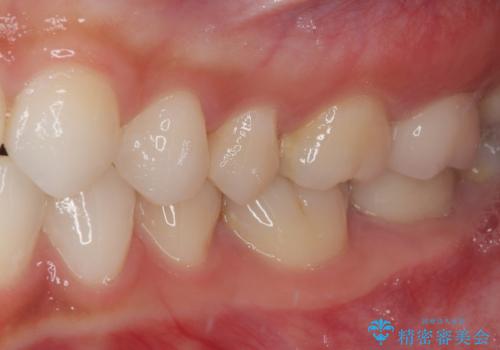

レジンが劣化してきた オールセラミッククラウン

- すごく前に治療したレジンがざらつくので治療したいとのことで来院された患者様です。十年ほど前に根管治療を行っており、症状は特に何もない状態でした。根管治療を行っている歯は咬合力に対して鈍くなり破折しやすくなるため、最終的には被せものによる補綴治療を行う必要があります。

ラバーダム防湿下でコンポジットレジンを除去しファイバーコア築造を行い、オールセラミッククラウンに適した形に整えました。

見た目、機能面共に大変喜んでいただきました。

精密な型どりを行った被せものは適合性も良いため虫歯の再発リスクを低減することが可能です。